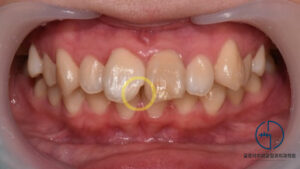

상봉역 교정치과 앞니 벌어짐 발치 교정 및 왜소치 라미네이트 과정

안녕하세요, 상봉역 교정치과 김정은 원장입니다. 왜소치에 대해 들어보신적 있으신가요? 왜소치는 말그대로 정상적인 치아크기보다 작게 형성된 이를 말합니다, 특히 앞니 부위에서 흔히 나타나며 치아 사이 공간이 남거나 비율이 어색해보이는 심미적 고민으로도…